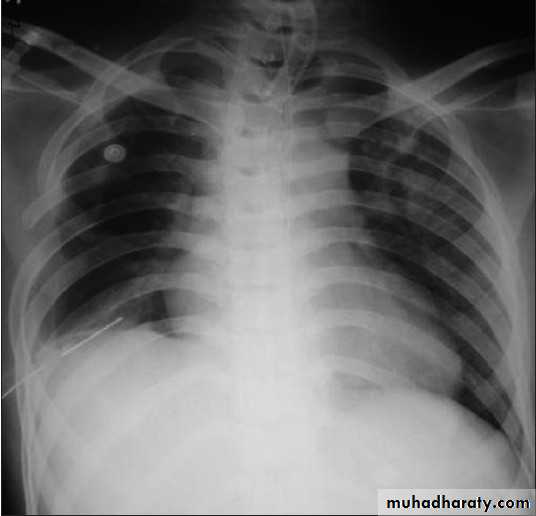

Pneumothorax

!! pneumothorax